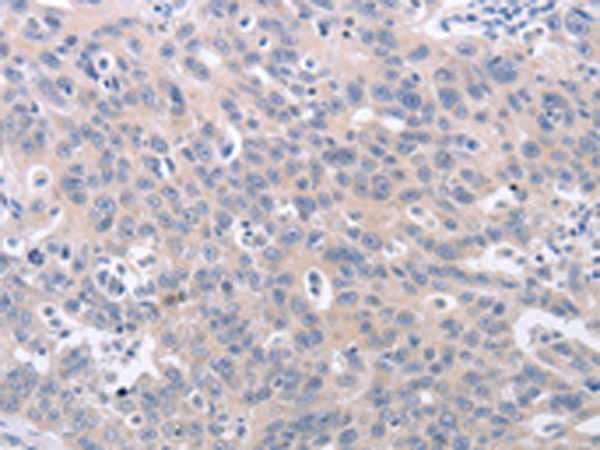

分类: 科研抗体货号: P07554别名:应用: IHC反应种属: Human, Mouse, Rat